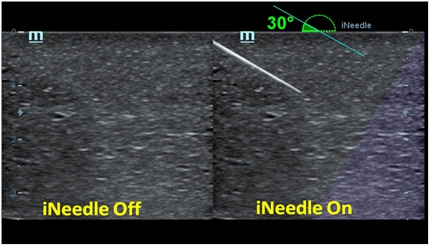

B-Steer/iNeedleTM

Your tool for deeper biopsy: allowing adjustments to the scan line to gain better visibility of the needle, nerves and small vessels.